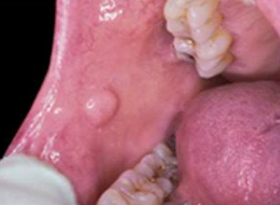

Gladstone, MO -- (SBWIRE) -- 04/21/2015 -- Oral cancer affects more than 42,000 people each year in the United States. Even more disturbing is the fact that the mortality rate of the disease has remained unchanged in over thirty years, due in part to late diagnoses. At Gladstone Family Dental Group, Dr. David Platt and Dr. Gregory Dale understand the importance of early detection and diagnosis in order to increase a patient's chances of survival.

Oral cancer screening is one of the most important aspects of routine dental exams at the practice and is included without any additional charge. "We perform a complete head and neck exam and an intra-oral cancer screening on every patient," says Dr. Platt, "Our aim is to detect possible oral cancer in its earliest stage. When patients skip their routine dental exams, they forget that they are also missing out on oral cancer screenings."

Many people only find out that they have oral cancer when it has already advanced beyond its preliminary stages. By then, it may already be too late.